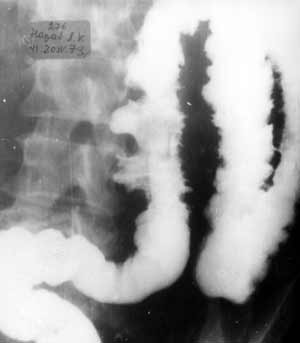

Рентгенологическая визуализация стенозов толстой кишки.

Рис. 2. Сегментарная форма болезни Крона.

Новости лучевой диагностики 1998 2: 7-9